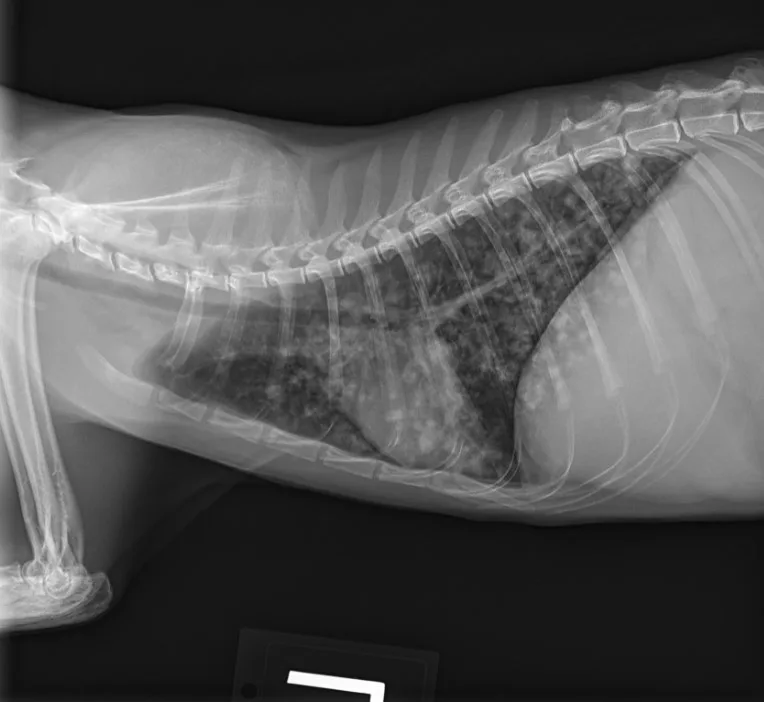

At the 1-month recheck, her weight had increased to 6 lb (3 kg); estimated BCS was 3/9. Physical examination showed a normal respiratory pattern, but increased bronchovesicular sounds were still present bilaterally. No fundic abnormalities were noted. Radiographs indicated subtle improvement of the diffuse nodular pulmonary pattern (Figure 2).

A

FIGURE 2 Left lateral (A), right lateral (B), and ventrodorsal (C) thoracic radiographs 1 month after initiation of itraconazole. Subtle improvement of the diffuse nodular pulmonary pattern can be seen.